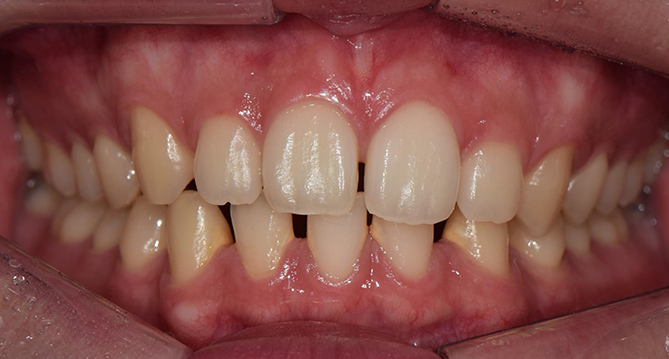

연세새빛치과 전체치아교정[클리피씨] 교정 전

연세새빛치과 전체치아교정[클리피씨] 교정 후